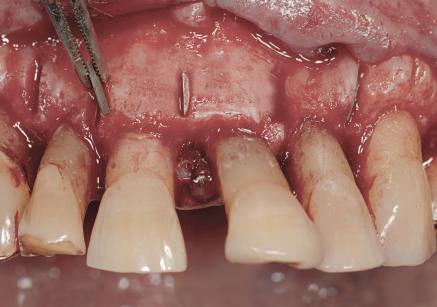

Dacă însă implanturile sunt plasate prea vestibular sau prea superficial, componentele nu permit un design adecvat al bontului, pentru că plasarea marginii este limitată iar conturul facial şi proximal poate fi compromis (fig. 1, 2).

Figurile 3, 4. Întrucât poziţia implantului era mezială faţă de ideal, bonturile individualizate s-au conceput plate pe profilul mezial, dar au prezentat provocări în privinţa conturării restauratoare. 5. Restaurările implantare de la nivelul 1.2. şi 2.2. susţin o FPD metalo-ceramică cimentată între incisivii laterali.

Figurile 1, 2. Compromisurile conturului vestibular şi proximal sunt evidente. Implantul este la nivel tisular, tehnicianul neputând gestiona plasarea marginii sau a profilului intrasulcular pentru a îmbunătăţi estetica. Dacă se concepea un design tradiţional cu hexagon extern, marginea restauratoare s-ar fi putut plasa foarte aproape de interfaţa bont-implant, cu gestionarea mai bună a spaţiului.